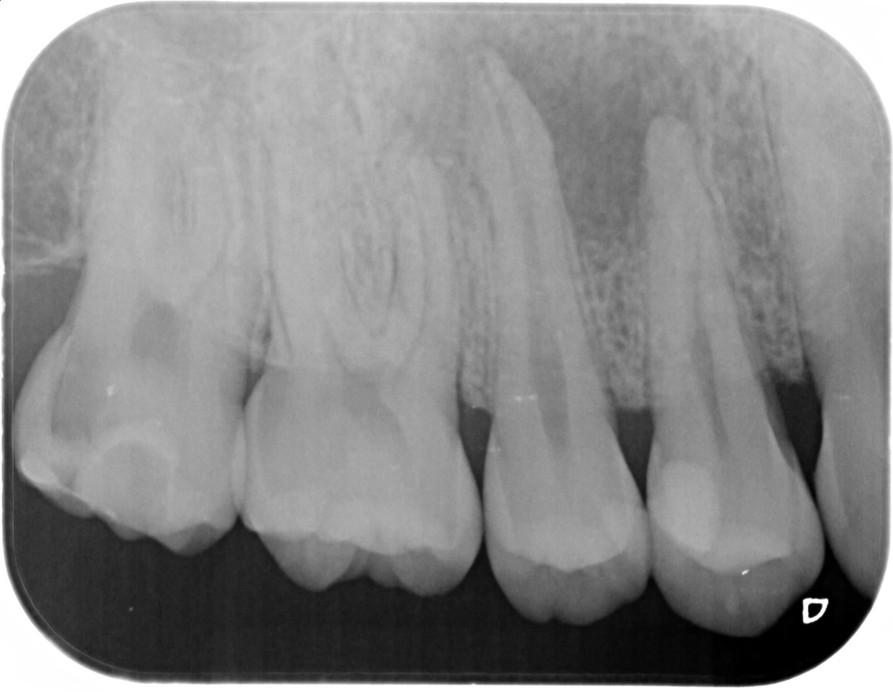

①![]() 術前 |

②![]() 根管治療後3か月経過 |

③![]() 根管治療後1年経過時 |

④![]() 根管治療後2年経過時 |

神経の治療後、①→②→③→④と時間をかけて徐々に治ってくることがあります。

神経の治療は細菌感染を除去する治療です。細菌がいなくなれば、無駄に神経をとらなくても良い歯もあるかもしれません。

| 患者様データ | 30代 男性 |

| 来院時の主訴 | 「他院で右上の歯3本とも神経をとる必要があると言われた。なんとか神経を残したい。」 |

| 術前検査結果 |

右上第一小臼歯:打診痛(+)・歯髄の生活反応有り 右上第二小臼歯:打診痛(+)・歯髄の生活反応無し 右上第二大臼歯:打診痛(ー)・歯髄の生活反応有り |

| 医院の診断 |

右上第一小臼歯:健全→術前に神経が残せる可能性のある歯と診断 右上第二小臼歯:慢性根尖性歯周炎→術前に神経が残せない歯と診断 右上第二大臼歯:無症候性可逆性歯髄炎→術前に神経が残せる可能性のある歯と診断し、術中に神経を残せると診断 |

| 通院期間 | 2年半 |

| 来院回数 | 10回(定期的なチェック含む) |

| 治療費 | 350,000円(税抜) 《内訳》 右上第二小臼歯:精密根管治療70,000円、ファイバーポストコア20,000円、セラミック治療120,000円 右上第二大臼歯:歯髄温存療法55,000円、セラミック治療85,000円 |

| リスクと副作用 | ①根管治療歯は長期的には破折するリスク ②メインテナンスが必要 |

| ココがこだわりのポイント☝ |

レントゲン検査や患者様の訴える症状だけでは神経を残せるかどうかは断定できません。 この方もレントゲン写真上では神経を残せないように見える歯でしたが、治療前に検査を入念に行うことで残せる可能性を見出すことができました。 同じ悩みを抱えた方は是非お気軽にご相談下さい。 |